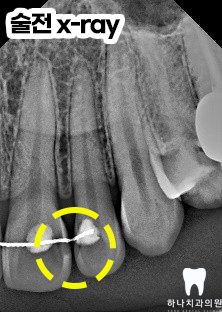

치아 교정 후 설측에 리테이너가

붙어 있는 상태로 위생 관리가 제대로

이루어지지 않아 위쪽 앞니와 옆 치아의

사이에 심한 우식으로 인해

심미성이 많이 떨어진 상태였습니다.

따라서 우식 정도가 미약한

옆의 앞니는 복합 레진 충전,

앞니는 크라운을 시행하는 것으로

계획을 수립하였습니다.

앞니에 발생하는 충치는 겉으로

쉽게 드러나지 않아 단지 작은 점이나

가느다란 선처럼 보이지만

실제로 내부에서는 상당히 진행된

상태일 수 있는데요.

겉에 드러난 변화가 작다고 해서

우식의 범위까지 작다고 단정 짓는 것은

매우 위험합니다.